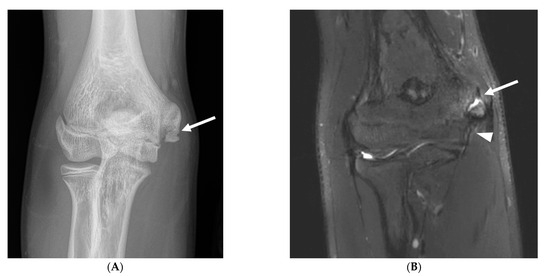

Figure 5.

A 15-year-old right-hand-dominant male baseball pitcher with right posterior elbow pain. (A) Sagittal fat-saturated T2-weighted image of the right elbow demonstrates irregularity, increased T2 signal and cystic change along the olecranon physis (open arrow), with periphyseal bone marrow edema, compatible with olecranon apophysitis. (B) Radiographic comparison of the bilateral elbows demonstrates physeal widening, irregularity, and delayed closure of the physis (open arrow) compared with the physis of the asymptomatic left elbow (arrow), which is partially fused superiorly.

Olecranon apophysitis was also only seen in athletes in subgroup 1 (Figure 5), with the exception of one athlete in subgroup 3 who had a chronic injury with associated nonunion of the olecranon apophysis, and olecranon stress reaction or fractures were observed with a higher frequency in subgroups 1 and 2 (12% and 24%, respectively), with a chronic injury seen in a single subject in subgroup 3. Other findings consistent with repetitive loading secondary to posteromedial shear and resultant degenerative changes in the posterior humeroulnar joint were observed with high frequency across all age groups, although this progressively increased with age. Specifically, humeroulnar osteophytes were observed in 62% of subjects in subgroup 1, 72% of subjects in subgroup 2, and 74% of subjects in subgroup 3 (Figure 6). This is in contrast to controls, where only 17% of subjects demonstrated posterior humeroulnar osteophytes.